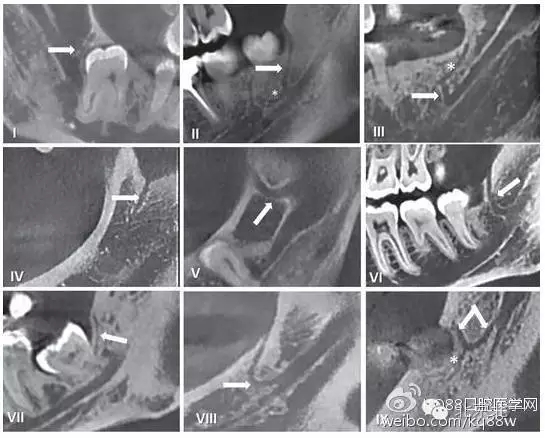

在臨床工作中,個體解剖差異導(dǎo)致像磨牙后管這類的神經(jīng)分叉及神經(jīng)走行的變化,術(shù)前只能通過放射方法檢測。但使用口腔曲面斷層片之類的常規(guī)二維影像學(xué)照片是難以檢查到的。隨著現(xiàn)代醫(yī)學(xué)影像技術(shù)的發(fā)展,出現(xiàn)了計(jì)算機(jī)斷層掃描(CT)和錐束CT(CBCT),其在口腔醫(yī)學(xué)領(lǐng)域的成功運(yùn)用使得磨牙后管的術(shù)前影像評估成為可能。精確的捕捉到下頜磨牙后管的解剖走行,需要高分辨率的成像設(shè)備并保證攝像期間患者沒有晃動。下面我們將用幾張CBCT影像圖片為大家圖示說明。

圖五 使用CBCT拍攝到的不同走行的下頜后管